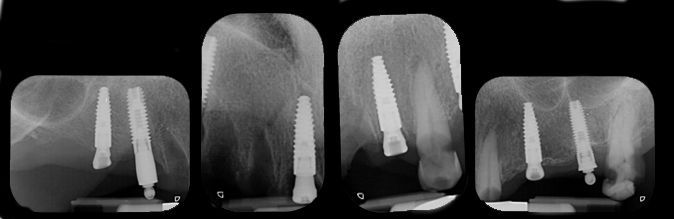

The postoperative x-ray images confirmed the precision of the implant placements in sites 16, 11, 22 and 25 (Fig. 40).

Fig. 40

Postoperative radiographs of the lower jaw were taken following implant placement, confirming proper positioning and angulation of the implants (Fig. 49).